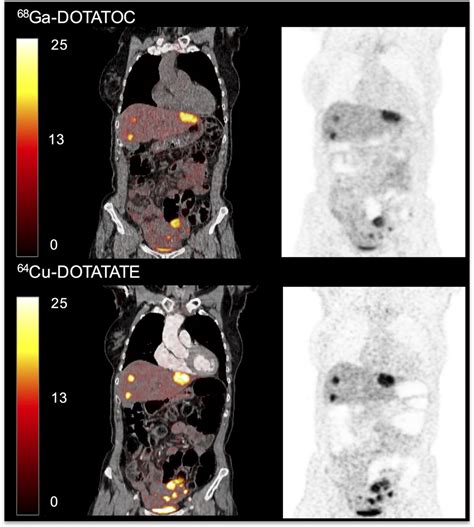

A Dotatate PET scan—often formally referred to as a Gallium-68 (Ga-68) DOTATATE PET/CT scan—is a sophisticated type of molecular imaging. Unlike conventional scans like CT or MRI, which primarily look at the size and shape of body structures, a PET scan focuses on how cells function at a molecular level.

The "Dotatate" component is a radioactive pharmaceutical agent. It acts as a targeted seeking device that binds to somatostatin receptors. These receptors are often found in high concentrations on the surface of neuroendocrine tumor cells. Because these tumors "light up" when the tracer binds to them, the PET scan creates a vivid map of where these tumors are located throughout the body, even those that are too small to be detected by standard imaging.

• Treatment Planning: By identifying precisely where the tumors are, surgeons or oncologists can better decide on the most effective course of treatment, such as surgery, radiation, or specialized medical therapies like peptide receptor radionuclide therapy (PRRT).

• Monitoring Progress: It can be used to assess how well a current treatment is working or to check for recurrence after treatment has been completed.

Once the scan is complete, the images are sent to a radiologist or nuclear medicine physician who specializes in interpreting these complex studies. They will analyze the images to identify areas of high tracer uptake, which indicate the presence of neuroendocrine tumor cells. The results are typically combined with findings from other tests and your clinical history to provide a comprehensive summary of your condition.